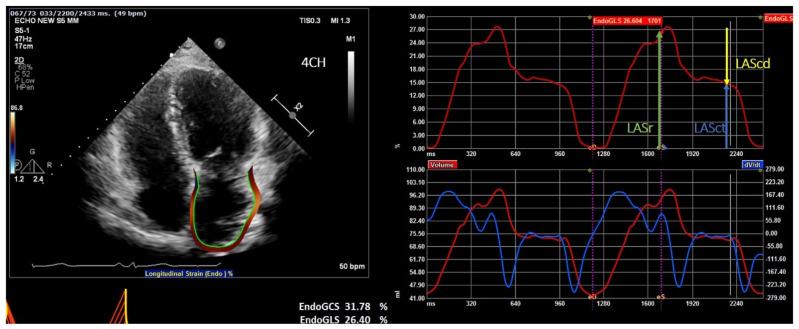

Methods: A prospective cohort of 32 patients with paroxysmal AF and structurally normal hearts, underwent either cryo- or radiofrequency ablation at a single tertiary center. Pre-ablation evaluations included LAS analysis via transthoracic echocardiography and LAAeV measurement via transesophageal echocardiography. Patients were followed for up to one year post-ablation, with recurrence defined as AF episodes lasting >30 seconds beyond a three-month blanking period. Statistical analyses assessed the predictive value of LAS and LAAeV, individually and in combination.

Results: AF recurrence occurred in 21.9 % of the cohort. Pre-ablation left atrial strain (LAS) values (global LAS ≥33.56 %, sensitivity 85.7 %, specificity 70 %, AUC = 81.4 %, P < 0.05) and left atrial appendage emptying velocity (LAAeV) (≥42.7 cm/s, sensitivity: 100 %, specificity: 87 %, AUC = 94 %, P < 0.001) were significantly associated with freedom from recurrence. The combination of LAS and LAAeV improved predictive accuracy to 100 % sensitivity and 94 % specificity (P value < 0.001). Post-ablation LAS showed inconsistent predictive value, with only apical-2 chamber global LAS achieving statistical significance (P = 0.002). Functional recovery of the left atrium post-ablation was minimal, suggesting limited reversibility of atrial remodeling.